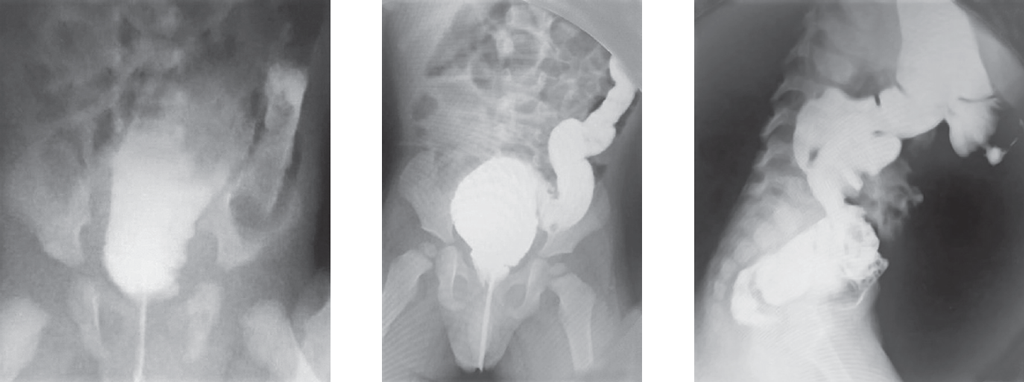

В хирургический стационар поступил ребенок на 2-е сутки жизни с клиникой кишечной непроходимости. По данным обзорной рентгенографии и ирригографии заподозрена болезнь Гиршпрунга (рис. 5, 6).

Рис. 5. Обзорная рентгенограмма брюшной полости

Fig. 5. Plain abdominal X-ray

Рис. 6. Ирригография

Fig. 6. Contrast enema

После выполнения высокой очистительной клизмы получено большое количество жидкого стула, газов, живот уменьшился в размерах. Планировалось продолжение консервативного лечения в виде ежедневных сифонных клизм и антибактериальной терапии. Однако через сутки произошло ухудшение состояния, наросло вздутие живота. Выполнены повторные рентгенограммы брюшной полости, выявлен свободный газ. Ребенок подготовлен к оперативному лечению в срочном порядке. При ревизии брюшной полости обнаружена перфорация толстой кишки в области илеоцекального угла. Восходящая и поперечно-ободочная кишки были умеренно расширены до 2–3 см, а от селезеночного угла до ректосигмоидного отдела кишка воронкообразно суживалась до 0,8–0,6 см. Интраоперационная картина соответствовала представлению о болезни Гиршпрунга, но оценить протяженность зоны аганглиоза не представлялось возможным. Нельзя было исключить тотальный аганглиоз толстой кишки, поэтому была наложена двойная илеостома и взята поэтажная биопсия толстой кишки, перфорационное отверстие ушито. Удивительными оказались результаты гистологического исследования, которое показало, что нервный аппарат толстой кишки сформирован правильно. Однако обнаружено тотальное грибковое поражение кишечной стенки во всех отделах, что, возможно, и явилось причиной перфорации толстой кишки. Послеоперационное течение без хирургических осложнений. Через 2 мес. выполнено закрытие илеостомы. Выздоровление.

Ирригография является обязательным исследованием у всех детей с подозрением на болезнь Гиршпрунга [2]. Чувствительность и специфичность метода по литературным данным достигает 70 и 80 % соответственно. Хорошо известно, что диагностическая значимость ирригографии в определении переходной зоны у новорожденных с болезнью Гиршпрунга меньше, чем у детей более старшего возраста (65 против 75 %) [3]. I.R. Diamond et al [4]. описали возможные предрасполагающие факторы получения ложноположительных результатов при выполнении контрастного исследования у пациентов с болезнью Гиршпрунга, одним из них является возраст ребенка. У детей в возрасте 30 сут жизни было больше ложноположительных результатов, чем у пациентов младшего возраста. Срок выполнения рентгенологического обследования зависит от нескольких факторов, главным из которых является эффективность опорожнения толстой кишки. Обследование целесообразно выполнять не сразу после поступления новорожденного в стационар, а отсроченно, после купирования явлений Гиршпрунг-ассоциированного энтероколита, чтобы исключить сужение кишки, связанное с ее спазмом на фоне воспалительных явлений. Конечно, это не касается ситуаций, когда есть клиника некупирующейся кишечной непроходимости, либо признаки «токсического» мегаколона. В этих случаях ирригография обязательно проводится непосредственно при поступлении ребенка в стационар. В остальных случаях, когда декомпрессия кишечника эффективна, исследование может быть отложено на несколько дней, до полной стабилизации состояния и нормализации клинико-лабораторных показателей. Контрастирование толстой кишки у детей с клиникой низкой кишечной непроходимости носит не только диагностический, но и лечебный характер, особенно при синдромах мекониальной пробки и суженной левой половины толстой кишки, которые могут быть причиной для постановки ложноположительного диагноза болезни Гиршпрунга. Надо отметить, что ирригография, выполненная в первые дни жизни ребенка сразу после появления клиники непроходимости, и отсроченное исследование могут отличаться друг от друга. На представленных рентгенограммах одного и того же ребенка с разницей в две недели видны существенные различия (рис. 8, а, b). Если на первичной ирригограмме можно оценить лишь правильность расположения толстой кишки и наличие в ней большого количества содержимого, то при исследовании через 2 недели видны четкие признаки ректосигмоидной формы болезни Гиршпрунга с наличием зоны сужения и воронкообразным супрастенотическим расширением.

Рис. 8. Ирригография; а — вторые сутки жизни; b — две недели жизни

Fig. 8. Contrast enema. а – second day of life; b – two weeks of life

Еще одним доводом за выполнение отсроченных ирригограмм у новорожденных с подозрением на болезнь Гиршпрунга может служить тот факт, что при раннем исследовании можно увидеть выраженное сужение толстой кишки, которое у новорожденного может быть признаком не только аганглиоза, но и иметь другие причины.

Считается, что чем более выражена разница в диаметре кишки при ирригоскопии, выполненной в первые дни жизни ребенка, тем менее вероятна болезнь Гиршпрунга. В этом плане очень показателен случай 3. В той ситуации дифференцировать болезнь Гиршпрунга от грибкового поражения толстой кишки до операции было практически невозможно. С подобной картиной мы встретились впервые. Рентгеноконтрастное исследование толстой кишки в данном случае не имело диагностической ценности.